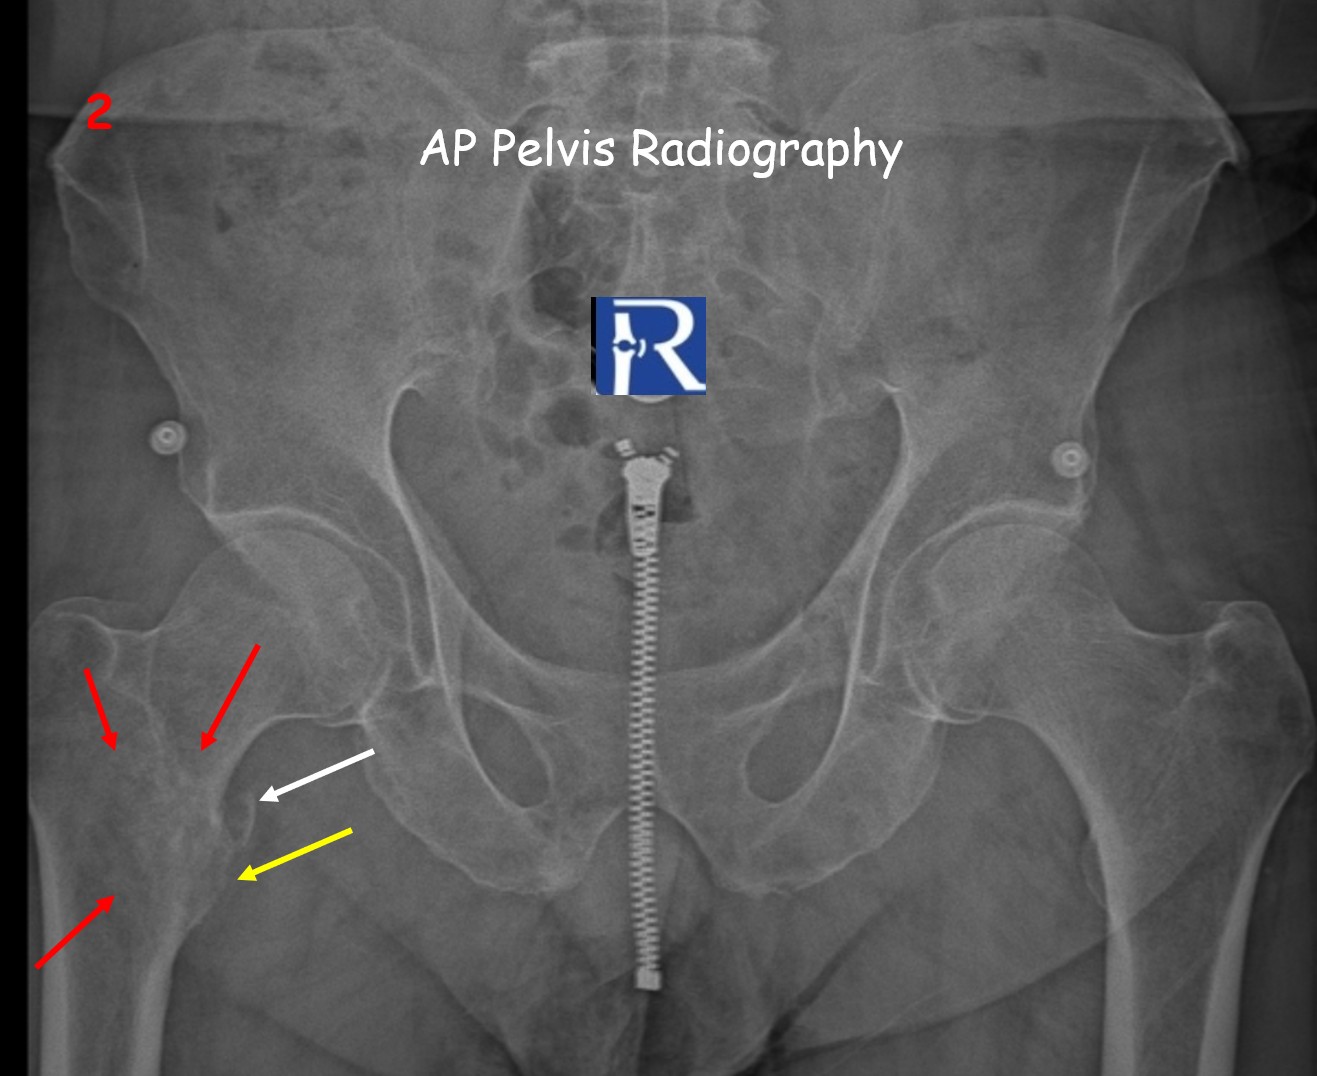

Plain radiography (Figures 1–2) demonstrated a displaced avulsion fracture of the right lesser trochanter with a cortical bone defect and a free bone fragment along the medial aspect of the femoral neck. Additionally, a permeative lytic pattern was observed in the intertrochanteric region.

⚪ White arrows → Avulsed bone fragment

???? Yellow arrows → Cortical defect at the lesser trochanter

???? Red arrows → Tumoral infiltration margins